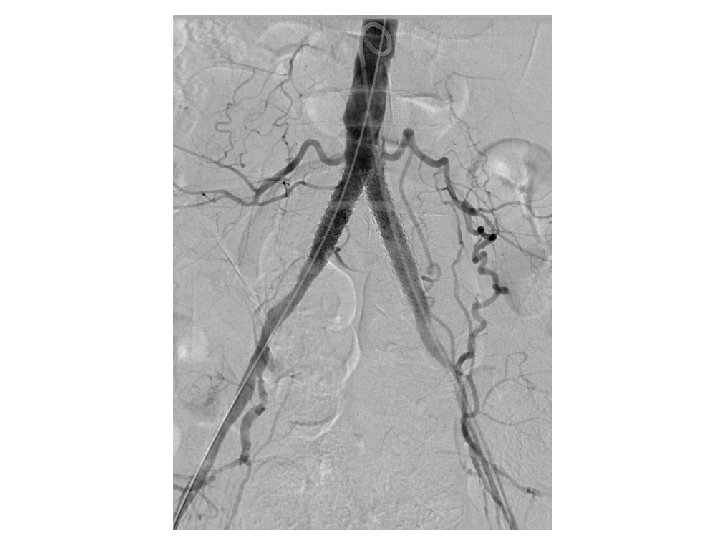

Kissing CBE Stents Still Essential With Distal Aorta Disease • In cases of aortic reentry—kissing stents insure both CIA have adequate flow • The farther the stents extend into the aorta (more that just touching) the more likely they are to narrow/occlude • Kissing Iliac stents should be BE CS (CS>>BMS) Sabri SS, et al. Outcomes of covered kissing stent placement compared with bare metal stent placement in the treatment of atherosclerotic occlusive disease at the aortic bifurcation. J Vasc Interv Radiol. 2010 Jul; 21(7): 995 -1003.

Single Versus Kissing Stents for Unilateral Proximal CIA Disease • Unilateral >50% CIA and 30%-50% in the contralateral CIA • 80 patients (69 males, 66. 6 years) treated with a single stent and 30 (26 males, 67. 1 years) treated with kissing stents • Two patients in the single-stent group (3%) required bailout kissing stents because of plaque shift to the contralateral side • Major complication rates: 8% in single-stent vs 13% in the kissing -stent group (P =. 399) • At 3 years, the single-stent and kissing-stents group had similar primary patency (89% vs 87%; P =. 916) and target lesion revascularization-free survival (93% vs 87%; P =. 462) Suh Y et al. Outcomes of the single-stent versus kissing-stents technique in asymmetric complex aortoiliac bifurcation lesions. J Vasc Surg. 2015; 62: 68 -74

Summary • Residual stenosis is important—get multiple views and consider IVUS and/or CBCT • Kissing stents probably not needed in every proximal CIA lesion, but CBE stents still first choice for bifurcation • Runoff quality, lesion length and calcification are best predictors of poor outcome > stent type